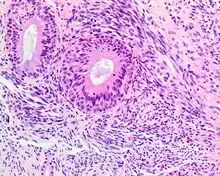

A high-power view of a hematoxylin- and eosin-stained slide showing respiratory epithelial inclusions within a spindled cell neoplasm showing characteristics of a biphenotypic sinonasal sarcoma